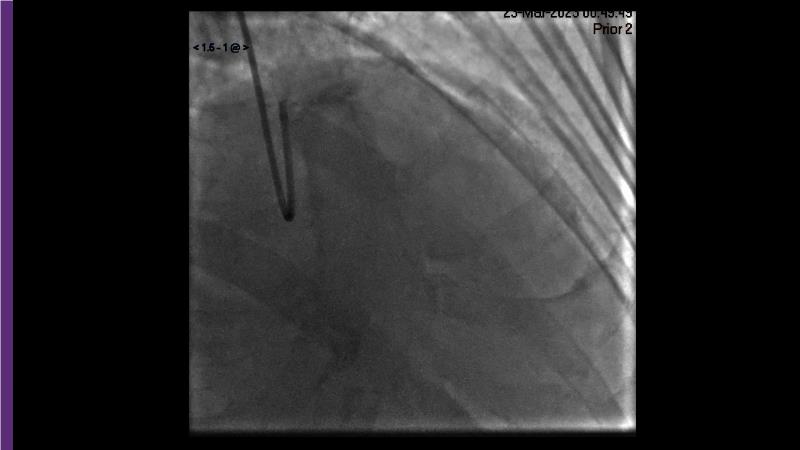

Browse this EuroPCR 2024 session to explore the safety and efficacy of sirolimus-coated balloons from pre-clinical data, review MagicTouch data from real-world populations with case-based examples, and learn about the MagicTouch sirolimus-coated balloon clinical programs. Discover insights and takeaways from the significance of the EASTBOURNE subgroups, and analyze the challenges and opportunities in PCI for diabetic patients.